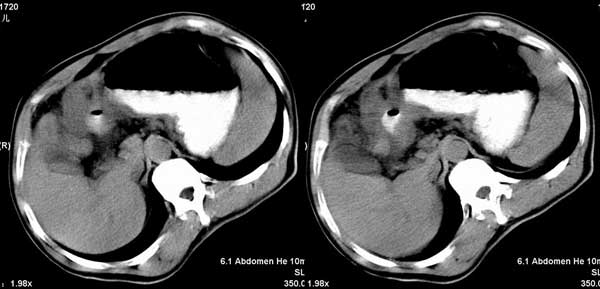

以下是引用听蝉观竹在2005-2-15 23:30:28的发言:[br]胃窦癌。[br]建议做胃镜检查并活检。